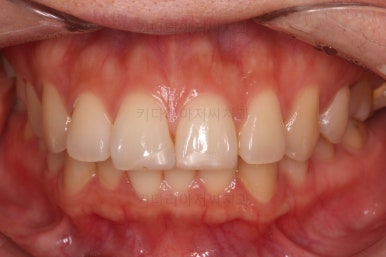

부산연산동교정치과 치료 종료 시의 모습이에요.

삐뚤한 치열도 가지런해졌고 2급 부정교합도 정상교합으로 맞춰졌어요.

튀어나와있던 앞니도 좋아졌고, 과개교합도 개선이 되었어요.

옆라인도 좋아졌고 입술을 다무는 느낌이 굉장히 편안해져서 입이 많이 들어간 건 아닌듯하지만 얼굴모습은 매우 좋아졌어요.

전후 사진을 비교해 보겠습니다.

전후 사진을 나란히 놓고 비교해 보면 굉장히 많이 좋아진 것을 볼 수 있으실거에요.

웃을 때의 치아의 위치를 보면 뒤로 들어간 것을 볼 수 있고, 이 영향으로 입매도 매우 예뻐졌고 편안해졌어요.

교합이나 치아배열의 모습도 좋아졌고요.

이상 발치교정을 통해 돌출입, 과개교합, 2급 부정교합을 개선한 부산연산동교정치과 사례였습니다.